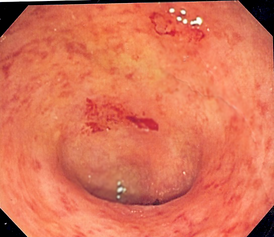

Так выглядит кишечник при воспалении

Язвенный колит, или неспецифический язвенный колит (НЯК) — хроническое воспалительное заболевание слизистой оболочки толстой кишки, возникающее в результате взаимодействия между генетическими факторами и факторами внешней среды, характеризующееся обострениями.